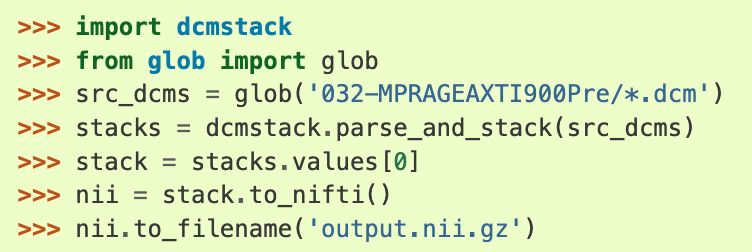

- dcmstack: Python编写的。它具有一个巧妙的功能,可以让你在NIfTI文件中存储/查看DICOM元头数据。dcmstack下载链接